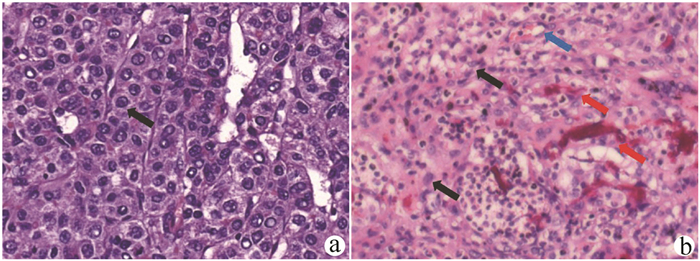

Construction of a new patient-derived xenograft model of human liver cancer in mice with normal immunity

Huixin TANG, Shanshan LI, Feng HONG, Yanzhen BI, Quanyi WANG, Xiaobei ZHANG, Shumin CHENG, Zhongping DUAN, Zhenfeng SHU, Yu CHEN

2021, 37(11): 2584-2588. DOI: 10.3969/j.issn.1001-5256.2021.11.019

Abstract(2380) HTML (628) PDF (3030KB)(167)

Abstract:

Objective  To establish a new patient-derived xenograft (PDX) model of human liver cancer by inoculating the complex of human primary liver cancer cells and a novel microcarrier (microcarrier 6) into mice with normal immune function.  Methods  Primary liver cancer cells were isolated and extracted from the fresh human liver cancer tissue of five patients and were then co-cultured with microcarrier 6 to construct a three-dimensional tumor cell culture model in vitro. According to the type of graft, 75 male C57BL/6 mice were divided into cell control group, microcarrier control group, and experimental group (each sample corresponded to three groups, with 15 groups in total and 5 mice in each group). The liver cancer cell-microcarrier complex was implanted into the mice by subcutaneous inoculation, and tumor formation time, tumor formation rate, and histopathological manifestations were observed. The Fisher's exact test was used for comparison of categorical data between two groups.  Results  As for the liver cancer cells from the five patients, tumor formation was observed in the mice corresponding to three patients. In these three experiments, tumor formation was not observed in the control groups and was only observed in the experimental groups, and 12 of the 15 mice in the experimental groups had successful tumor formation, with a tumor formation rate as high as 80%, which was significantly different from that in the cell control groups and the microcarrier control groups (all P < 0.05). The tumor formation time was 5-7 days; the xenograft tumor grew rapidly, and HE staining showed nested or flaky cells with obvious heteromorphism, with the presence of pathological mitosis; immunohistochemical staining showed positive CK8/18, Hep, and Gpc-3, which was in accordance with the characteristics of human liver cancer cells.  Conclusion  This experiment successfully establishes a new PDX model of human liver cancer based on the complex of microcarrier 6 and human primary liver cancer cells in mice with normal immunity. This model can be used to better elucidate the mechanism of the development and progression of liver cancer in the body with normal immunity, and besides, it also provides a new animal model with higher value for the precise treatment of liver cancer.